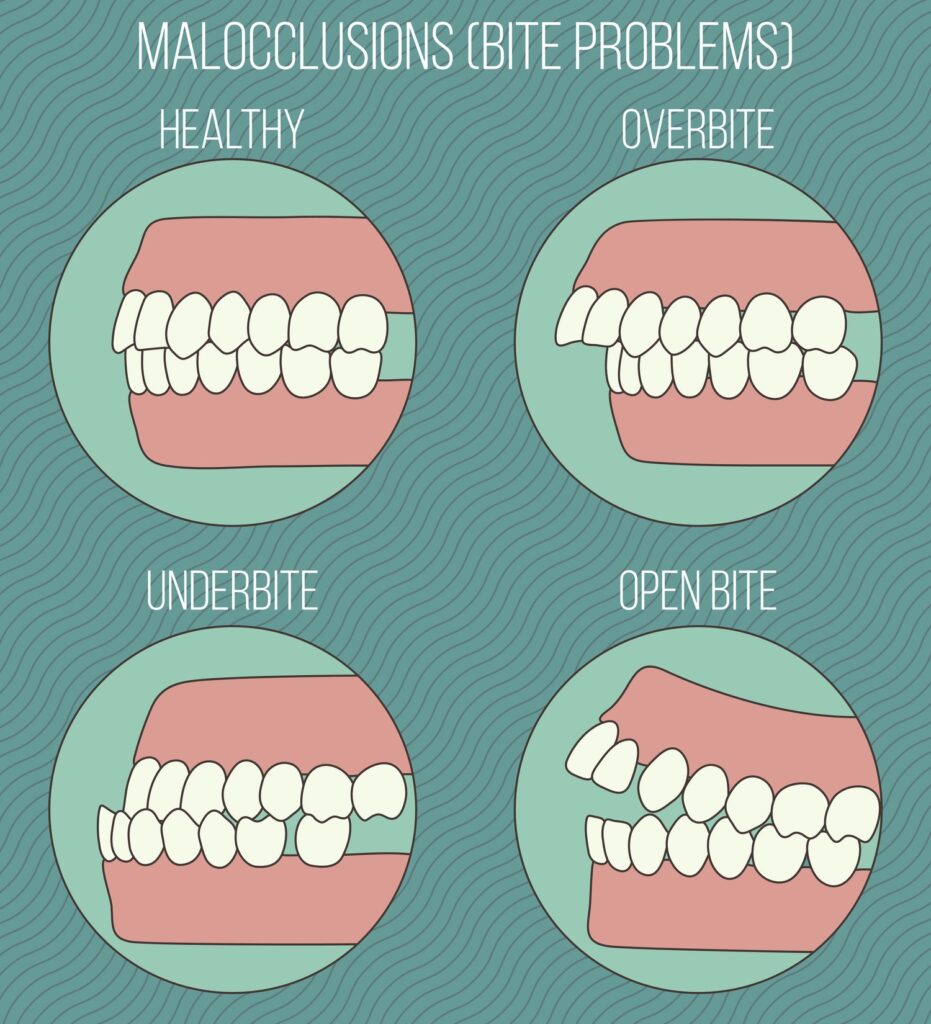

Patients with mild to moderate orthodontic issues are best suited for clear aligners including:

-Teeth gaps

-Overbite

-Underbite

-Bite through

Conventional braces or other orthodontic procedures, however, can be necessary in difficult situations requiring substantial tooth movement or problems with jaw alignment.